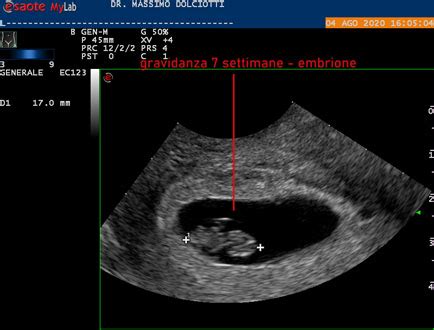

Nel primo trimestre, la CRL è la misurazione più comunemente utilizzata per stimare l'età gestazionale. Le prime otto settimane della gravidanza rappresentano la fase dell’embriogenesi, un’epoca molto delicata, in quanto, in questo periodo, si sviluppano i rudimenti di quasi tutti gli organi vitali, come il cuore. Fino all’ottava settimana circa, lo zigote, la prima cellula che si forma dall’incontro dei due gameti provenienti da mamma e papà, va incontro a una rapida crescita formando l’embrione, che si sviluppa ulteriormente dando luogo a un organismo più complesso. Solo a partire dalla nona settimana di gestazione, si inizia a parlare di feto, momento in cui il suo sviluppo consiste nell'insieme di fenomeni che permettono l’accrescimento e l’organizzazione delle strutture che formeranno il corpo del neonato.

Comprendere a quale età gestazionale corrisponda una Lunghezza Vertice-Sacro (CRL) di 6mm è fondamentale per le future mamme e per gli specialisti, poiché permette di posizionare correttamente la gravidanza nel suo inizio. Sulla base delle tabelle di crescita fetale standardizzate, una CRL di 6mm corrisponde generalmente a un'età gestazionale di circa 6 settimane e 2-3 giorni. Questa è una fase molto precoce dello sviluppo embrionale, in cui il piccolo è ancora un embrione.

In questa fase, sebbene le fattezze siano ancora abbozzate, i rudimenti di quasi tutti gli organi vitali cominciano a svilupparsi. Già all'ottava settimana, per esempio, la lunghezza del feto è di circa un centimetro (10mm) e lo sviluppo del cuore è già completo, con la presenza di occhi, naso e bocca. Una misurazione di 6mm indica che si è ancora un po' prima di questo stadio, con un embrione in rapida evoluzione ma ancora molto piccolo. È importante sottolineare che queste stime sono indicative e l'andamento complessivo della crescita è sempre più rilevante del singolo valore misurato in un preciso momento. I ginecologi si confrontano con tabelle che riportano l’andamento di crescita in percentili proprio per avere un quadro completo e dinamico dello sviluppo.